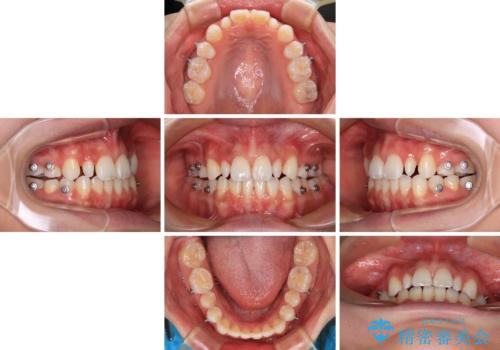

治療途中で地元へ転居され、飛行機での通院となったため、治療期間が長くなりましたが、自然で整った口元に仕上げることができました。

上下前歯同士の距離が離れているため、上顎左右第一小臼歯2本を抜歯することで前突を改善することとしました。

しかしながら、左右ともに側切歯が矮小歯であるため、矯正治療で矮小歯前後にスペースを作り、矯正治療後にオールセラミッククラウンにて補綴治療を行うこととしました。